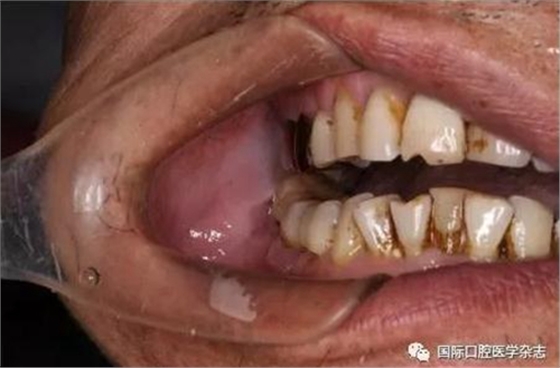

(1)急性下頜第三磨牙冠周炎(圖7):多見于青年人,早期感覺局部牙齦輕微疼痛。如炎癥進(jìn)一步發(fā)展波及咀嚼肌群,尤其是進(jìn)入翼下頜間隙和咬肌間隙,侵犯翼內(nèi)肌和咬肌時(shí)可發(fā)生不同程度的張口受限,并可合并全身癥狀,如發(fā)熱、寒戰(zhàn)、白細(xì)胞增多等。

圖 7 第三磨牙冠周炎